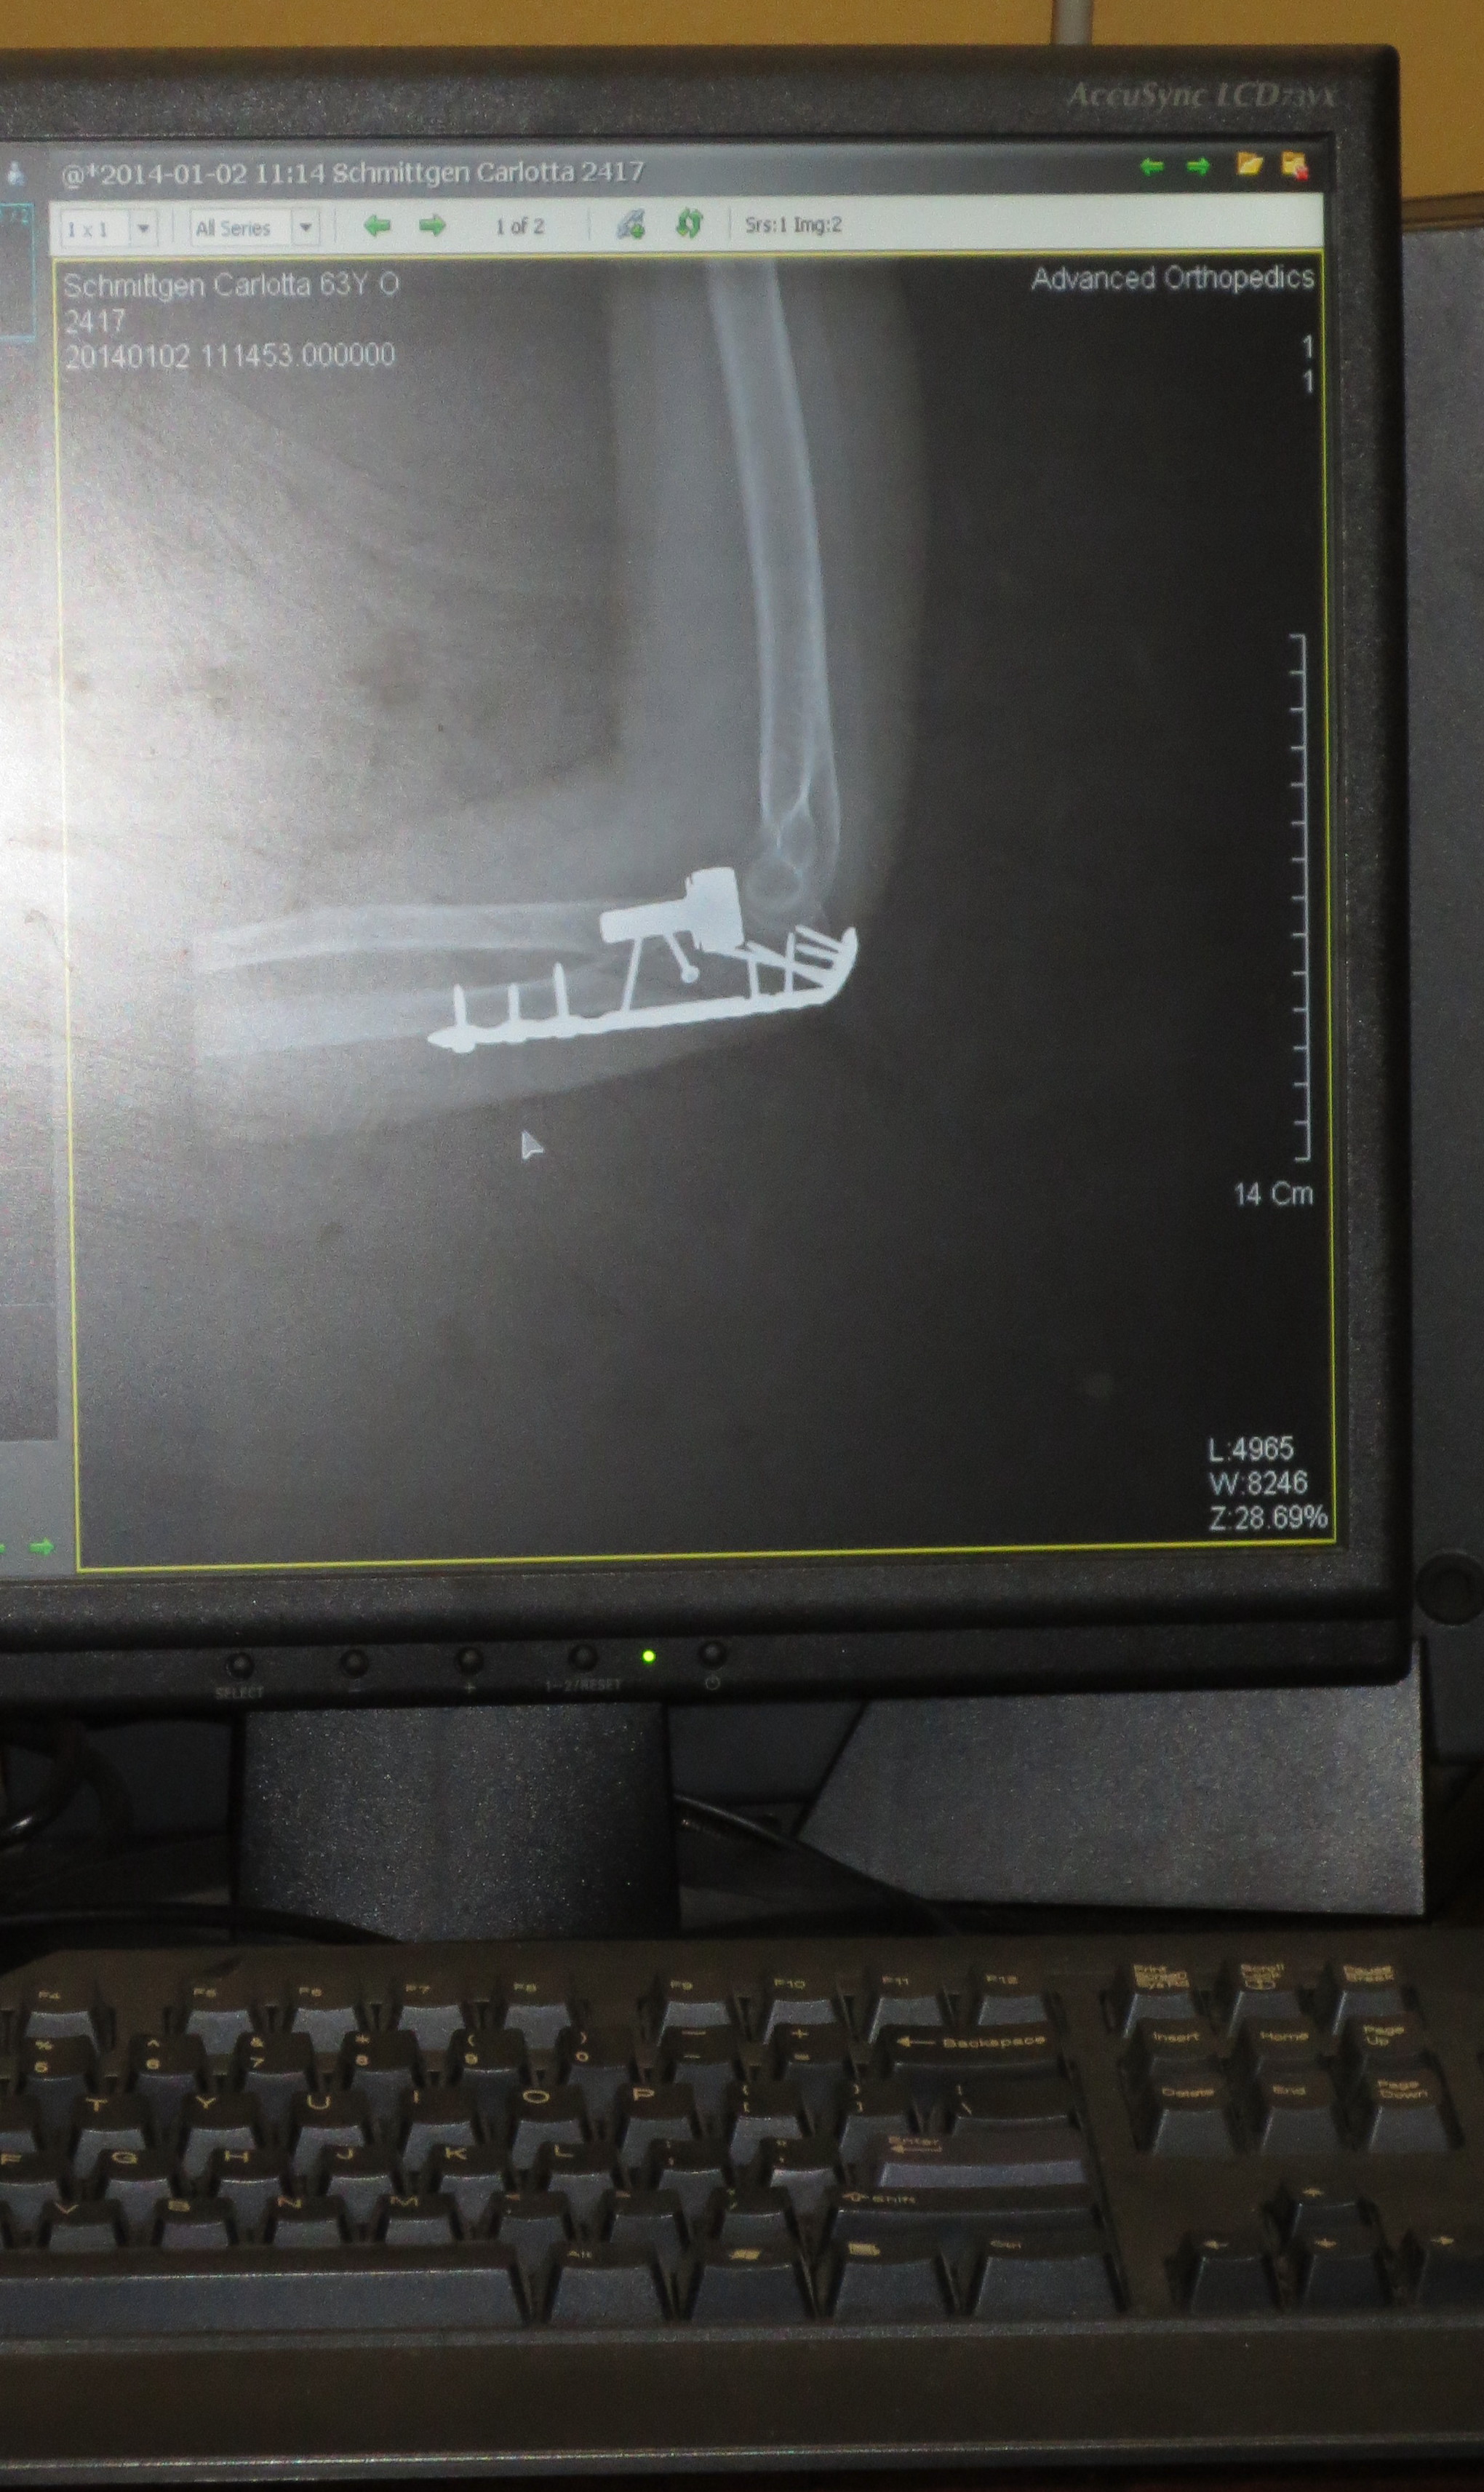

Fast forward to the second week of December and my next doctor’s visit. Dr. Lue was pleased with the healing of my left elbow and shoulder. Not only was I getting to go home, but I acquired a contraption for my elbow instead of the sling. Remembering my interest in football, Dr. Lue proudly communicated that it was the device football players wore when they returned to the playing field after elbow surgery. The next thing I knew I nestled in an almost two-foot mechanism which felt like about ten pounds on my arm. It was locked in ninety degrees forcing my elbow to stay in place. Do think there was a problem with the dogs jumping on me after I got home? Hardly! Rex wouldn’t even get within two rooms of me!